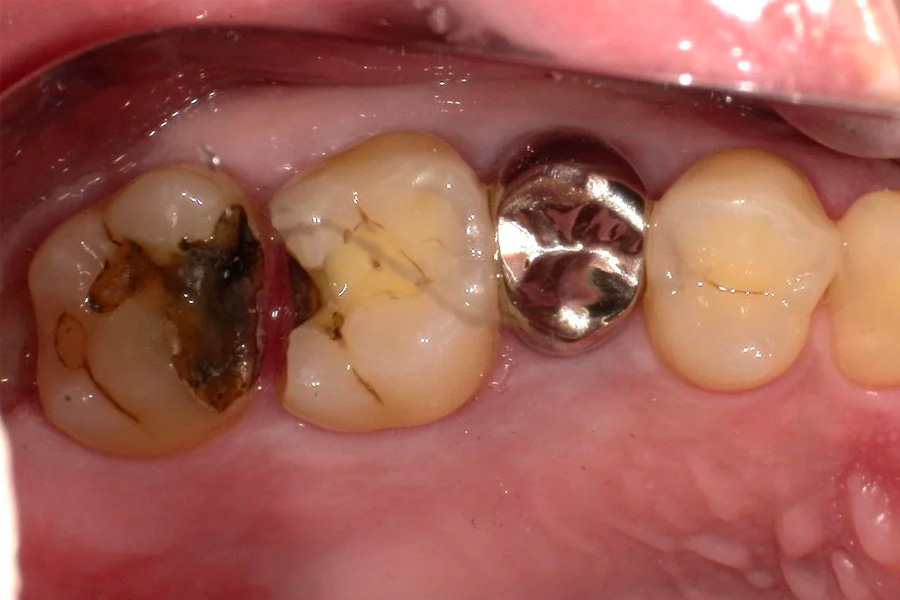

治療前

治療中

(銀歯を外した後)

主訴 虫歯を治したい。白く強度のあるものにしたい。

治療内容 右上4.5.6番目の虫歯を除去し、セラミックインレーを装着しました。